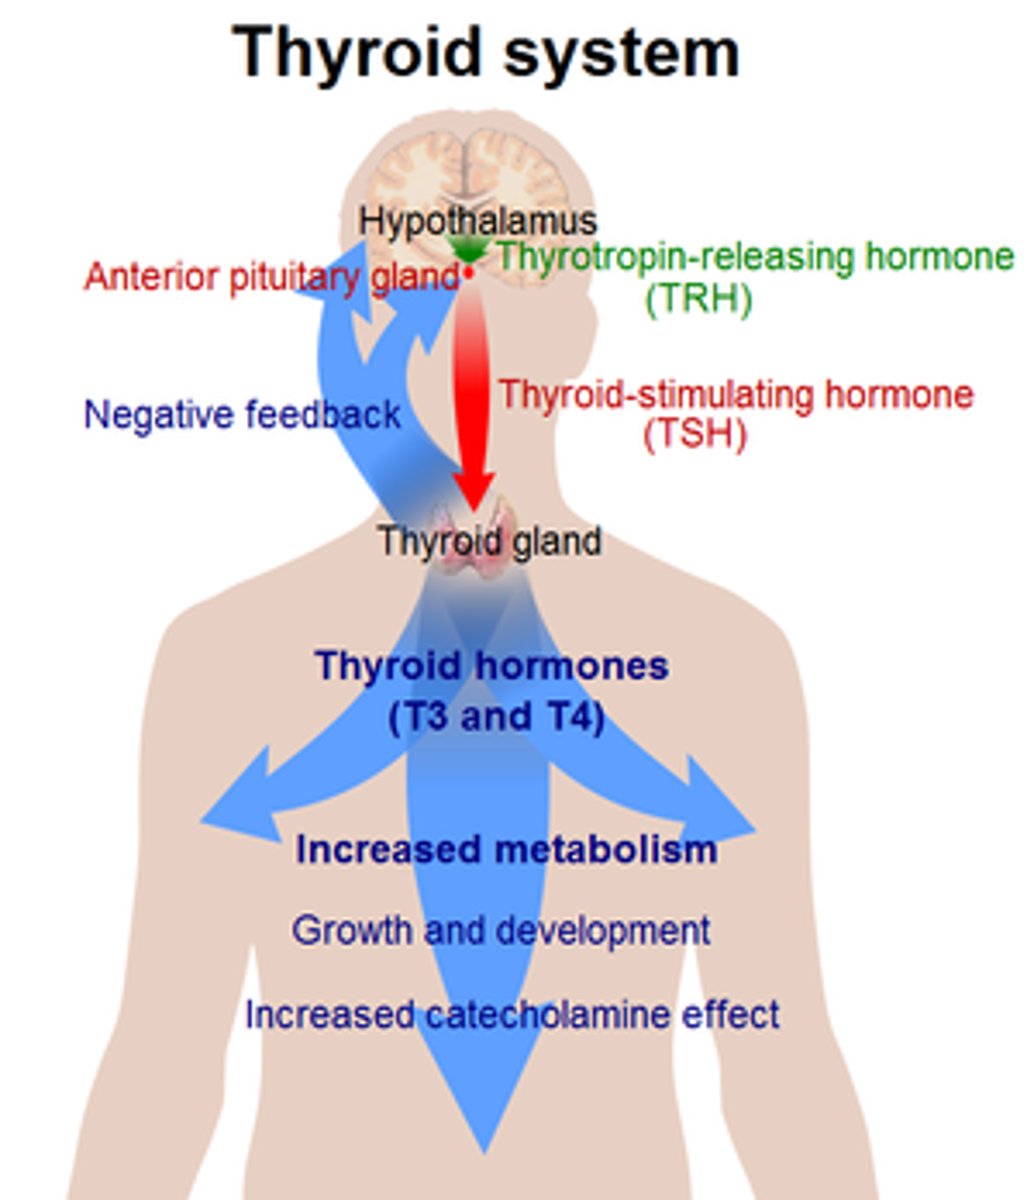

thyroid gland

endocrine gland that surrounds the trachea in the neck

hypothalamus hormones

ADH, oxytocin, regulatory hormones

pituitary gland hormones

LH, FSH, GH, TSH, ACTH, Prolactin, Oxytocin, ADH

thyroid hormones

T3, T4, calcitonin